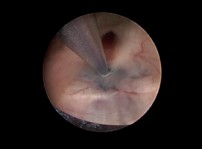

Superato il forame di Monro si ispeziona il pavimento del III ventricolo (formato dal chiasma ottico, il tuber cinereum con l'infundibolo, i corpi mammillari e la sostanza perforata posteriore) identificando l'area del tuber cinereum, tra il recesso infundibolare anteriormente e la salienza dei corpi mammillari posteriormente (fig. 4); al di sotto può intravedersi la biforcazione dell'apice dell'arteria basilare.

La ventricolostomia è in genere effettuata anteriormente all'arteria basilare. Le tecniche proposte per il suo confezionamento sono varie. la più utilizzata è la perforazione (fig. 5) e l'allargamento della stomia con un palloncino cilindrico del Fogarty 3 Fr (fig. 6 e fig. 7).